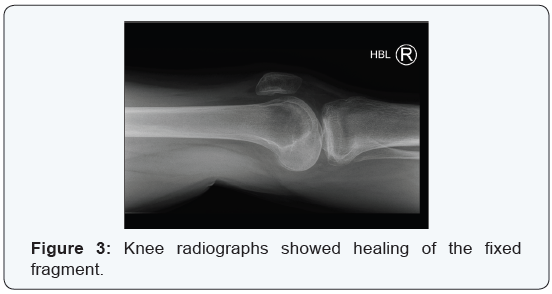

maintaining non-weight bearing. He was then allowed to flex from 0-90 and progress to partial weight bearing, for 6 weeks. After this, he was allowed free flexion and full weight bearing mobilisation under physiotherapist supervision, avoiding contact sport, while encouraging swimming and cycling. MRI scan of the knee performed 10 months post operatively demonstrated osseous union of the fragment (Figure 6). There was also some superficial fibrillation of the chondral component, but at no point was this full thickness. Clinically at final follow up at 12 months, he had a pain free, full range of movement. He was discharged back to previous levels of activity and sport.